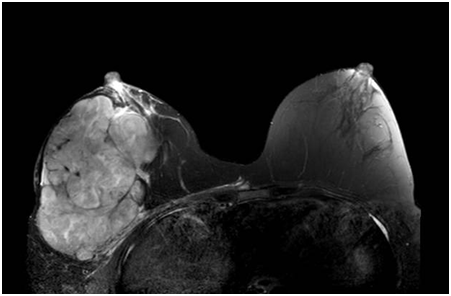

據了解,劉女士是在一年前開始發現右側乳房有一個黃豆大小的腫物,當時未予引起重視,直到幾個月前,感覺瘤子一下子變大了,并且一天比一天大,才匆匆忙忙來醫院檢查。劉女士穿著寬松的上衣,右手托著右胸,緩緩走進病房,邊走邊喘著氣。掀開上衣,眼前的一幕驚呆了查體的管床醫生,整個右乳被腫瘤占據,測量約有20cm,皮膚發紅,足足比左側乳房大了一倍。眼前的這個巨大的腫瘤,不僅僅影響到劉女士的工作生活,最重要的是,還不明確性質。

張敏敏副主任當即與科室負責人莫軍揚主任醫師以及科室成員協商進一步的診療方案,根據經驗,這個未知的炸彈傾向于葉狀腫瘤或者乳腺癌,結合患者的B超、鉬靶及磁共振檢查,先給劉女士做右乳腫物的穿刺,及皮膚活檢,病理回報為良性的葉狀腫瘤,紅腫的皮膚也未見癌成分,但由于穿刺取材有限,具體的結果需要完整的標本來確診。病理結果讓劉女士看到了希望,在嚴密的計劃之后決定手術切除這個重如泰山的“石頭”。手術的難度在于瘤體太大,剝離需要十分仔細且耐心。

完善好術前準備之后,張敏敏副主任帶領年輕醫生們加班加點,歷時3小時,在凌晨之前順利完成了這場“卸彈儀式”。術中發現胸大肌及肋骨已經被壓迫得輕微變形。術后乳腺甲狀腺外科一病區醫護團隊細心照料,劉女士順利出院,幸運的是,術后的病理結果也是良性的葉狀腫瘤。出院前拉著醫生的手不住道謝:“張醫生,真的很感謝你,這一路對我的照顧,我現在輕松多了,不會被壓得喘不過氣了,謝謝,真的謝謝!”